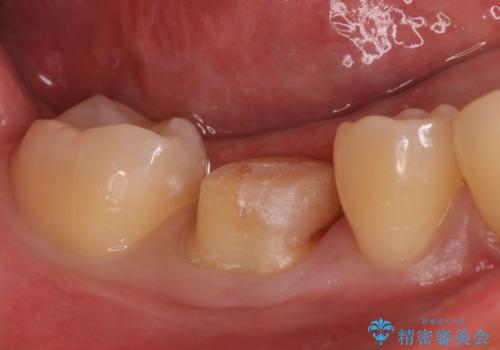

- 歯が欠けたとの事で来院。プラスチックの樹脂で治療されたところが欠けていて中に虫歯が再発していました。

古い樹脂と虫歯を拡大鏡下でしっかり取り除き、ジルコニアクラウンにて治療しました。